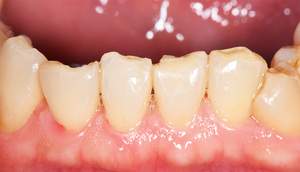

歯石除去

治療前

治療後

| 年齢 | 36歳・男性 |

| 主訴 | 歯石をとりたい |

| 治療内容 | 歯石除去 |

| 治療期間 | 30分 |

| 費用 | 約2,000円 |

| リスク・副作用 | ・歯ぐきの炎症が強いと歯石を取る際に出血することがあります。 ・処置後に歯がしみることがあります。 ・歯と歯の間に隙間ができるので、息が漏れ発音しにくいと感じることがあります。 ・歯ぐきの炎症が軽減すると歯ぐきが引き締まり、歯が長く見えることがあります。 |